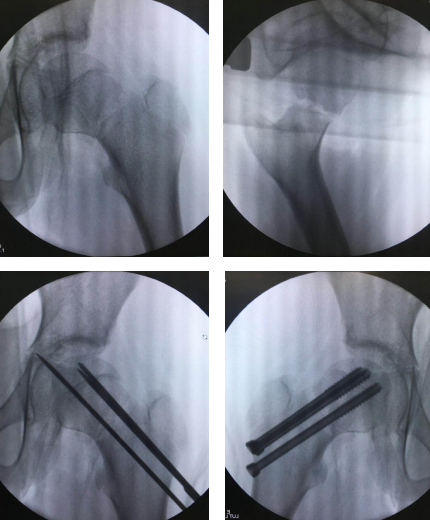

完善的术前准备后,手术开始。机器人“C臂”术中透视对小患者的股骨颈部位进行三维扫描,图像被同步传输至骨科手术机器人系统。同时,在导航系统屏幕上规划好钉道。随后,机器人的机械臂将手术工具精确定位到手术位置,套筒指向目的钉道的进钉点。任海东主任张子阳张恒军医生团队沿着套筒钻入导引针,确认位置无误后,置入3枚空心加压螺钉并通过导引针固定,拔出导针。C型臂透视,骨折对位对线良好,活动左髋关节无阻碍感及异常弹响,手术顺利结束。

以往股骨颈骨折如何精准置钉一直是个难题,但在机器人导航辅助下,手术团队将精确度误差控制在0.2毫米以内。整个手术过程,透视次数大幅减少,对患者及医护人员的放射保护大大增强。创口仅1厘米,术后患者几乎感觉不到疼痛。